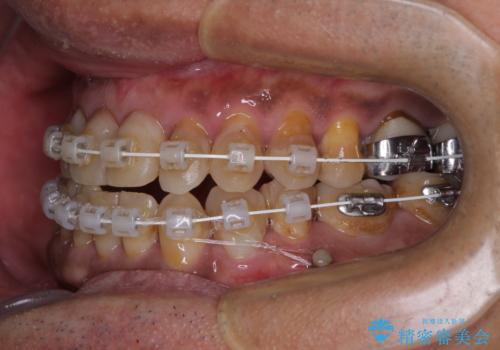

- 前歯のクロスバイトを気にして来院された患者様です。

40代男性で、インプラント補綴治療も経験されている方で、矯正治療をしても良いのかと悩んでいらっしゃいました。

下顎骨の左右のずれがあり、下顎全体が前方に出ている状態であったので、無理をせずにワイヤー装置にて矯正治療を行うこととしました。

クロスバイト改善には難儀しましたが、咬みやすく、笑ったときに清潔感ある口元に仕上げることができました。